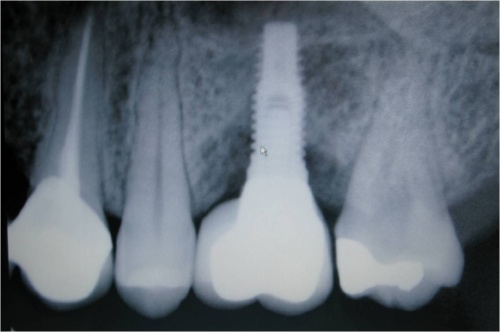

Resultado de colocação de implante dentário na Clínica São Filinto

São realizados exames complementares de diagnóstico, nomeadamente radiografia panorâmica dos maxilares (ortopantomografia) e TAC (tomografia axial computorizada) - quando necessário -, por forma a selecionarmos quais os melhores implantes dentários a utilizar. A escolha da melhor solução para um implante dentário depende, essencialmente, da qualidade e da quantidade de osso disponível.

Caso 1 - Implante imediato após extração do dente fraturado (dente 11) e implante imediato

![]() |